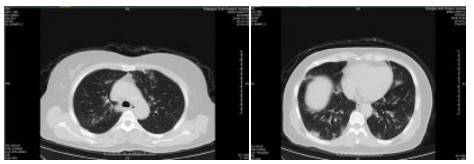

| 图 2 患者,女性,64岁,武汉籍,发病前1 d由武汉自驾车入沪,出现发热,体温39.9℃, 伴全身乏力,无咳嗽症状,无鼻塞,流涕症状,血白细胞总数及淋巴计数正常,甲乙型流感病毒筛查阴性,新型冠状病毒核酸检测阳性,肺部CT双肺多发磨玻璃结节,部分贴近胸膜,左肺有少量胸腔积液,局部小叶间隔增厚, 可见纤维条索影 Fig 2 Case 2, female, 64 years old, born in Wuhan. One day before the onset of the disease, she drove into Shanghai from Wuhan and had fever. Her body temperature was 39.9℃, with general asthenia, no cough, no nasal obstruction and running nose, normal WBC and lymphoid count, negative influenza A and B virus screening, positive novel coronavirus nucleic acid test. Lung CT showed multiple ground glass nodules, some of which were close to pleura, a small amount of pleural effusion in the left lung, and local interlobular septa was thickened, with visible fibrous streak shadow |

| 图 3 患者,女性,49岁,沪籍,发热10 d,体温最高38.5℃,伴乏力,肌肉酸痛,既往体健。否认武汉流行病学接触史,有菜场买菜史。血白细胞总数及淋巴计数正常,甲型、乙型流感筛查阴性,新型冠状病毒核酸检测阳性。肺部CT提示双肺磨玻璃结节,可见血管充血,增粗,穿行,部分贴近胸膜,伴小叶间隔增厚 Fig 3 Case 3, female, 49 years old, born in Shanghai, had fever for 10 days, body temperature 38.5℃, with fatigue, muscle pain, previous physical fitness. She denied the history of epidemic exposure of Wuhan, but had the history of shopping in market. Normal WBC and lymphoid count, negative influenza A and B virus screening, positive novel coronavirus nucleic acid test. Lung CT showed bilateral ground glass nodules with hyperemia, thickening and passage of blood vessels. Some were close to pleura with thickening of interlobular septum |